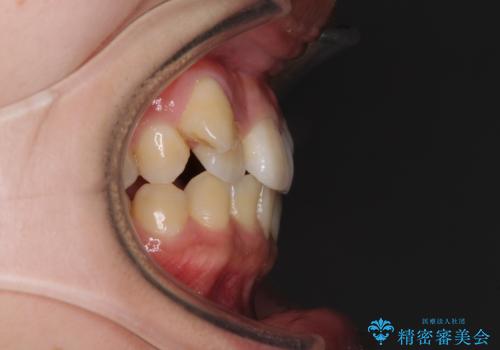

八重歯の抜歯矯正 補助装置を用いたインビザライン矯正

- 下の前歯のデコボコを気にして来院された患者様です。

来院当初、上顎の八重歯は気にしていらっしゃらなかったのですが、矯正治療をするのであれば、しっかりと治した方が良いと説明し、全顎矯正を行うこととしました。

八重歯の移動量が多く、インビザライン単体での治療は困難と判断し、補助装置により八重歯移動後にインビザラインを用いることとしました。